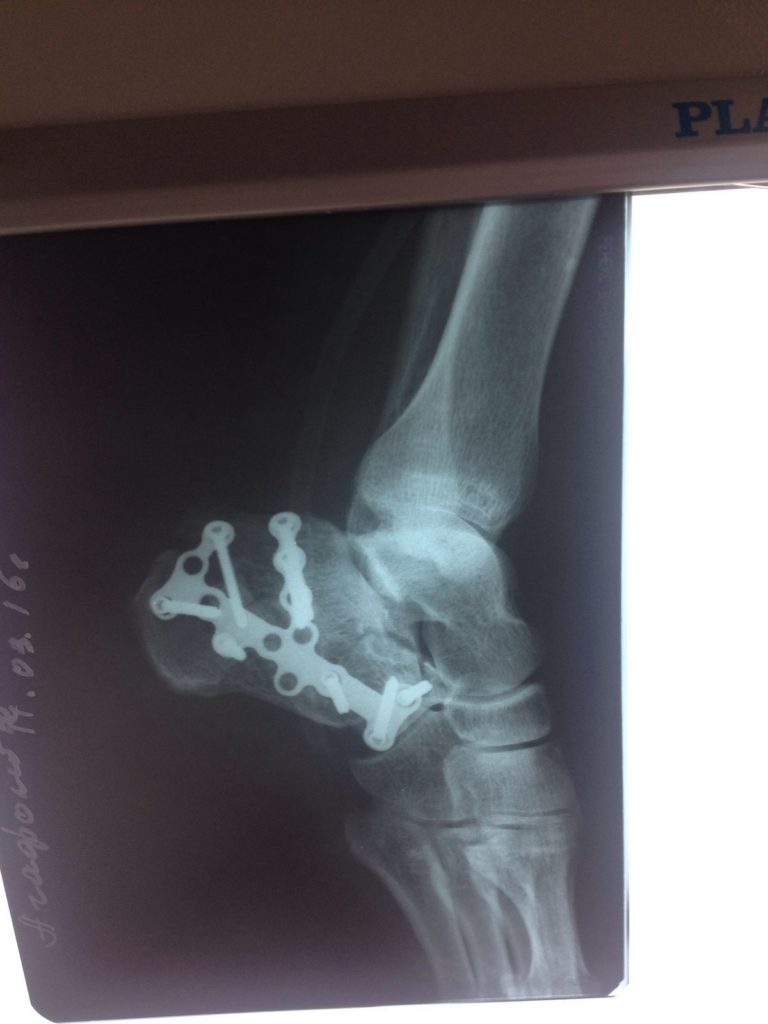

Операция – открытая репозиция, остеосинтез пяточной кости пластиной с костной ксенопластикой материалом «Остеоматрикс». На контрольных снимках в три месяца имеется консолидация перелома, миграции фиксатора нет, имеется остеоинтеграция ксенопластического материала.

Отдаленные результаты через 3 (три) месяца: